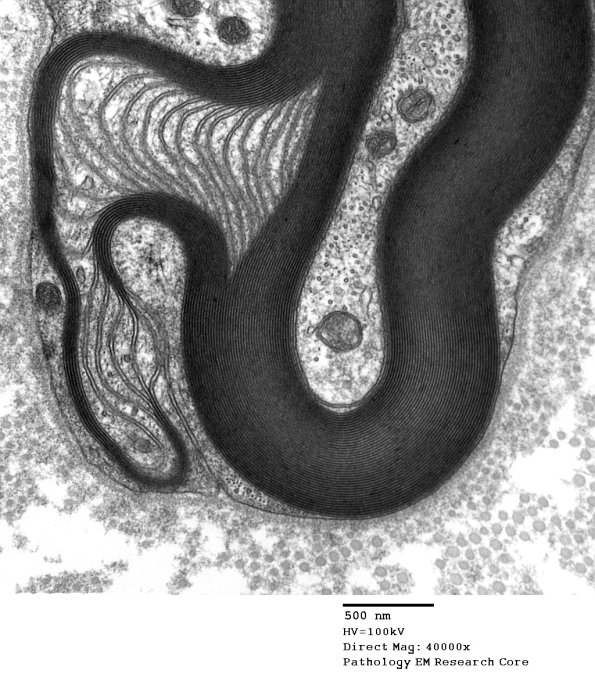

I think this is a Schmidt-Lanterman cleft, a few microtubules (arrowheads, 4C2C) often occupy the Schwann cytoplasm in S-L clefts. (electron micrographs)